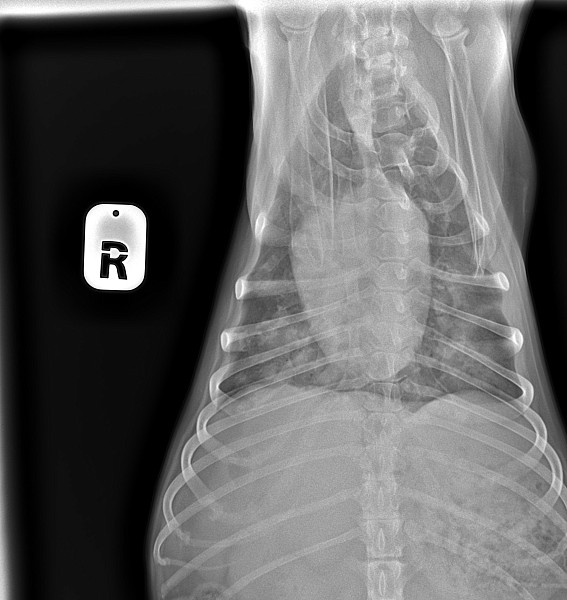

Добрый день!собачка кобель цвергпинчер 14 лет 10 месяцев,стал часто дышать,сделали рентген,помогите понять что с ним!

Добрый день!ренген лёгких у собаки помогите прояснить ситуацию!сделали в связи с частым дыханием

Здравствуйте, у собаки выраженное затемнение по каудальным долям легких. Более всего это похоже на пневмонию.